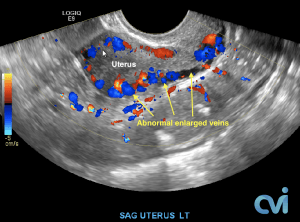

The abnormal veins dilate and cause varicose veins around the ovary and uterus because the valves don’t work properly. Blood flow is in the wrong direction, pooling in the veins and causing them to enlarge.

PCS can be diagnosed by Ultrasound or CT of the Abdomen and Pelvis.

Ultrasound examination is the least invasive study and can identify enlarged veins around the uterus and pelvis. However, sometimes the veins in the pelvis are difficult to see or can be missed if the technician is not specifically looking in the right area.

Magnetic resonance imaging (MRI) and computed tomography (CT) is another method to diagnose pelvic congestion syndrome. Our practice requires a CT of the Abdomen and Pelvis with contrast prior to treatment. This allows us to see where the varicose veins are coming from so that we can plan and do the appropriate treatment. Sometimes there are abnormal pelvic veins in addition to the ovarian veins that need treatment. Sometimes PCS can be missed on CT if the contrast injection is not timed appropriately or the vein is not directly measured.